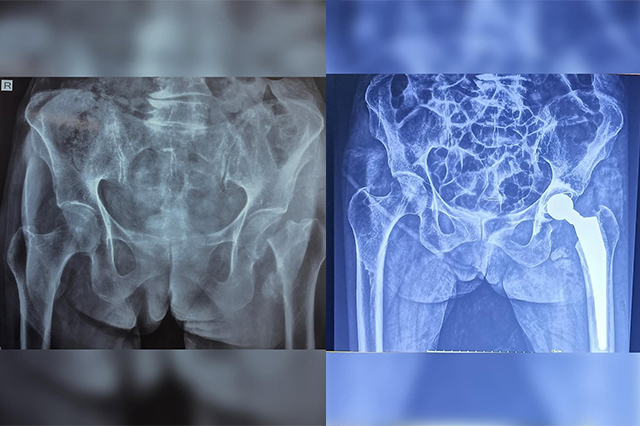

Hip-Knee-Replacement